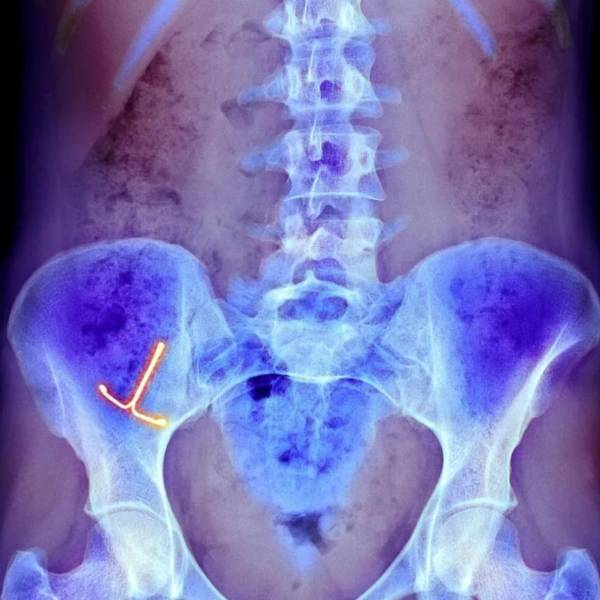

Una radiografía muestra un dispositivo anticonceptivo intrauterino  en el  vientre de una mujer

Los típicos objetos extraños vaginales incluyen dispositivos anticonceptivos intrauterinos dañados.

Los típicos objetos extraños vaginales incluyen pesarios o dispositivos anticonceptivos intrauterinos dañados que la paciente puede haber olvidado, o que no se haya dado cuenta de que están dañados.

Estos representan riesgos a largo plazo en forma de infecciones, fístulas (una apertura anormal entre un órgano hueco y otro o entre un órgano hueco y la superficie de la piel), y la formación de cálculos.